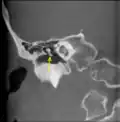

![]() A membrana timpânica direita com o martelo e a corda do tímpano, vista de dentro, por trás, e de cima. (Martelo visível no centro.) | |

CT imagem de martelo. -